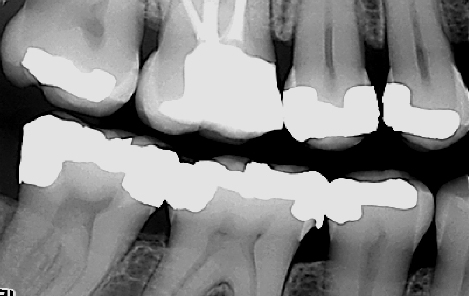

Røntgenbilder viser blant annet begynnende hull, behandlingskrevende hull, gamle fyllinger og tennenes benfeste